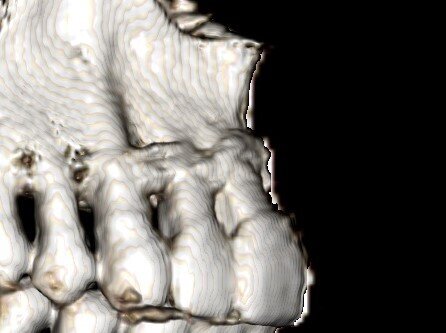

Fig.5: 3 D rendition of CBCT at 1 yr showing increased buccal bone support

The results of the study were noteworthy. While there was no significant difference between the two groups in terms of BOP, CAL, PD, and GR, Group A showed positive outcomes in other parameters. The thickness of the keratinized mucosa (TKM) increased by 1.76 mm in Group A but decreased by 1 mm in Group B. Similarly, the width of keratinized mucosa (WKM) saw a significant increase in Group A, from 2.86 mm to 3.6 mm. Furthermore, the thickness of the labial cortical plate also increased significantly in Group A, from 0.94 mm to 1.95 mm, whereas it decreased in Group B. There was no significant difference in pain perception between the two groups, indicating that the CAPD procedure did not cause additional discomfort.

While traditional treatments have been effective for infrabony defects, horizontal bone loss has remained challenging to treat. The CAPD technique appears to offer a valuable method for enhancing periodontal health in teeth affected by horizontal bone loss. This new technique allows for grafting on the buccal aspect, effectively addressing fenestrations/dehiscence defects while increasing the zone of keratinized tissue, a breakthrough for a condition that was previously not amenable to such treatment. The results suggest that CAPD can significantly improve the thickness of the gingiva and the bone, potentially leading to better long-term outcomes for patients.